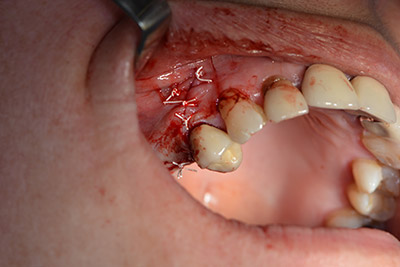

Хирургична процедура за имплантиране

Класическият разрез (крестално, букално освобождаване) и подготовката на мукопериостално ламбо осигуряват добра видимост.

Използвана е абсорбираща мембрана като бариера на букалната страна и покритие на аугментацията. Накрая са поставени устойчиви на слюнка конци (Фиг. 15 до 19).